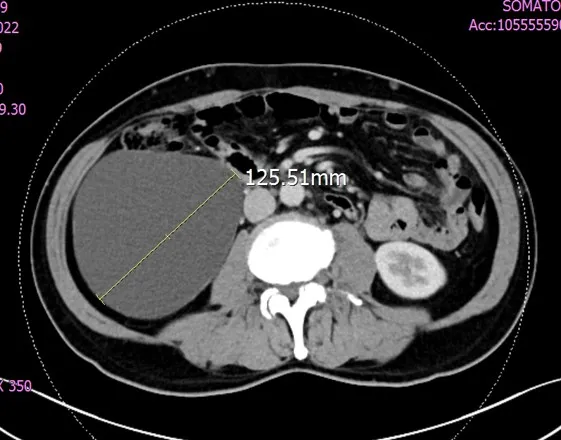

治療前12.5公分腫瘤。奇美醫院提供